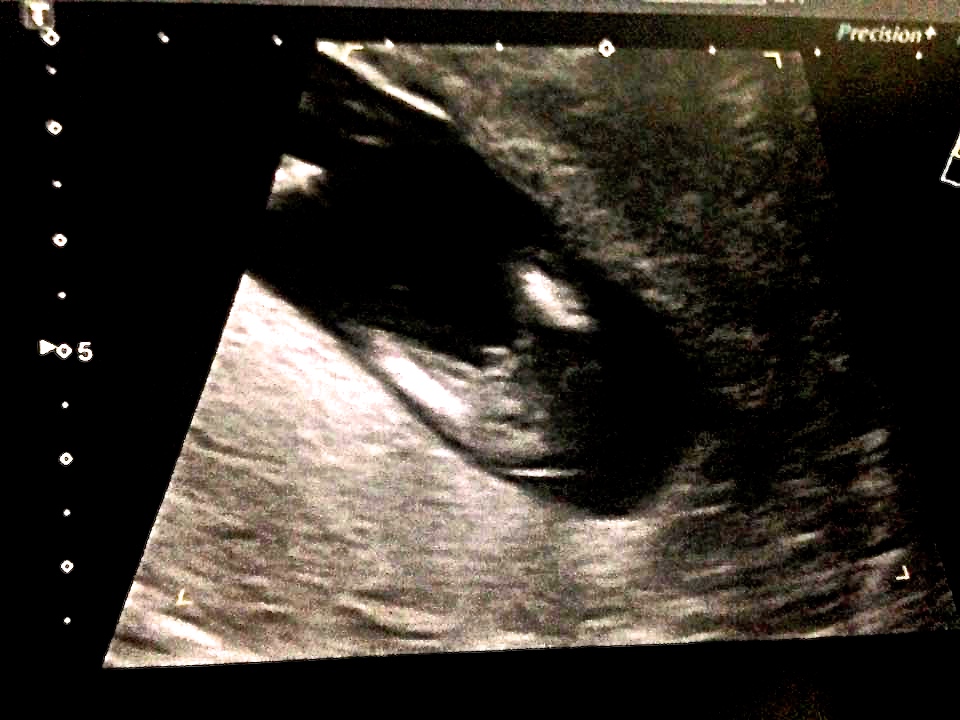

Boy!

The nub looks very girly. The potty shot is a bit confusing but you can't rely on that this early. I've seen very boyish looking potty's turn out to be girls. So my guess is girl!